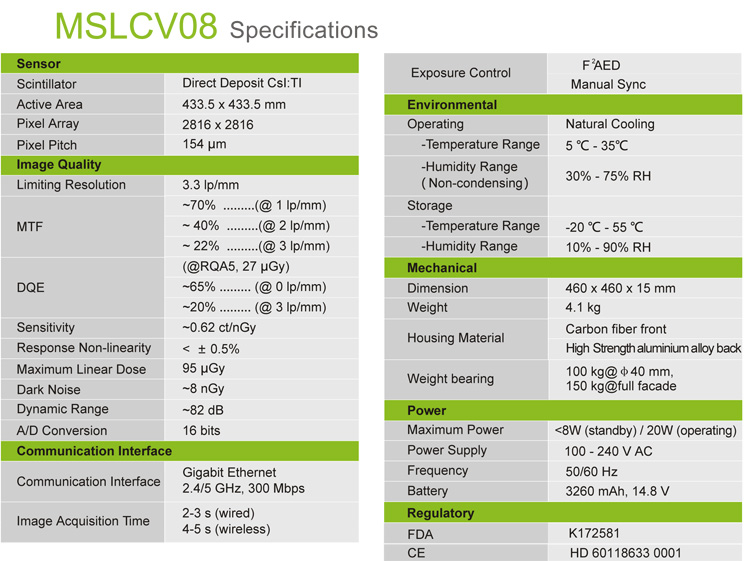

Product parameters